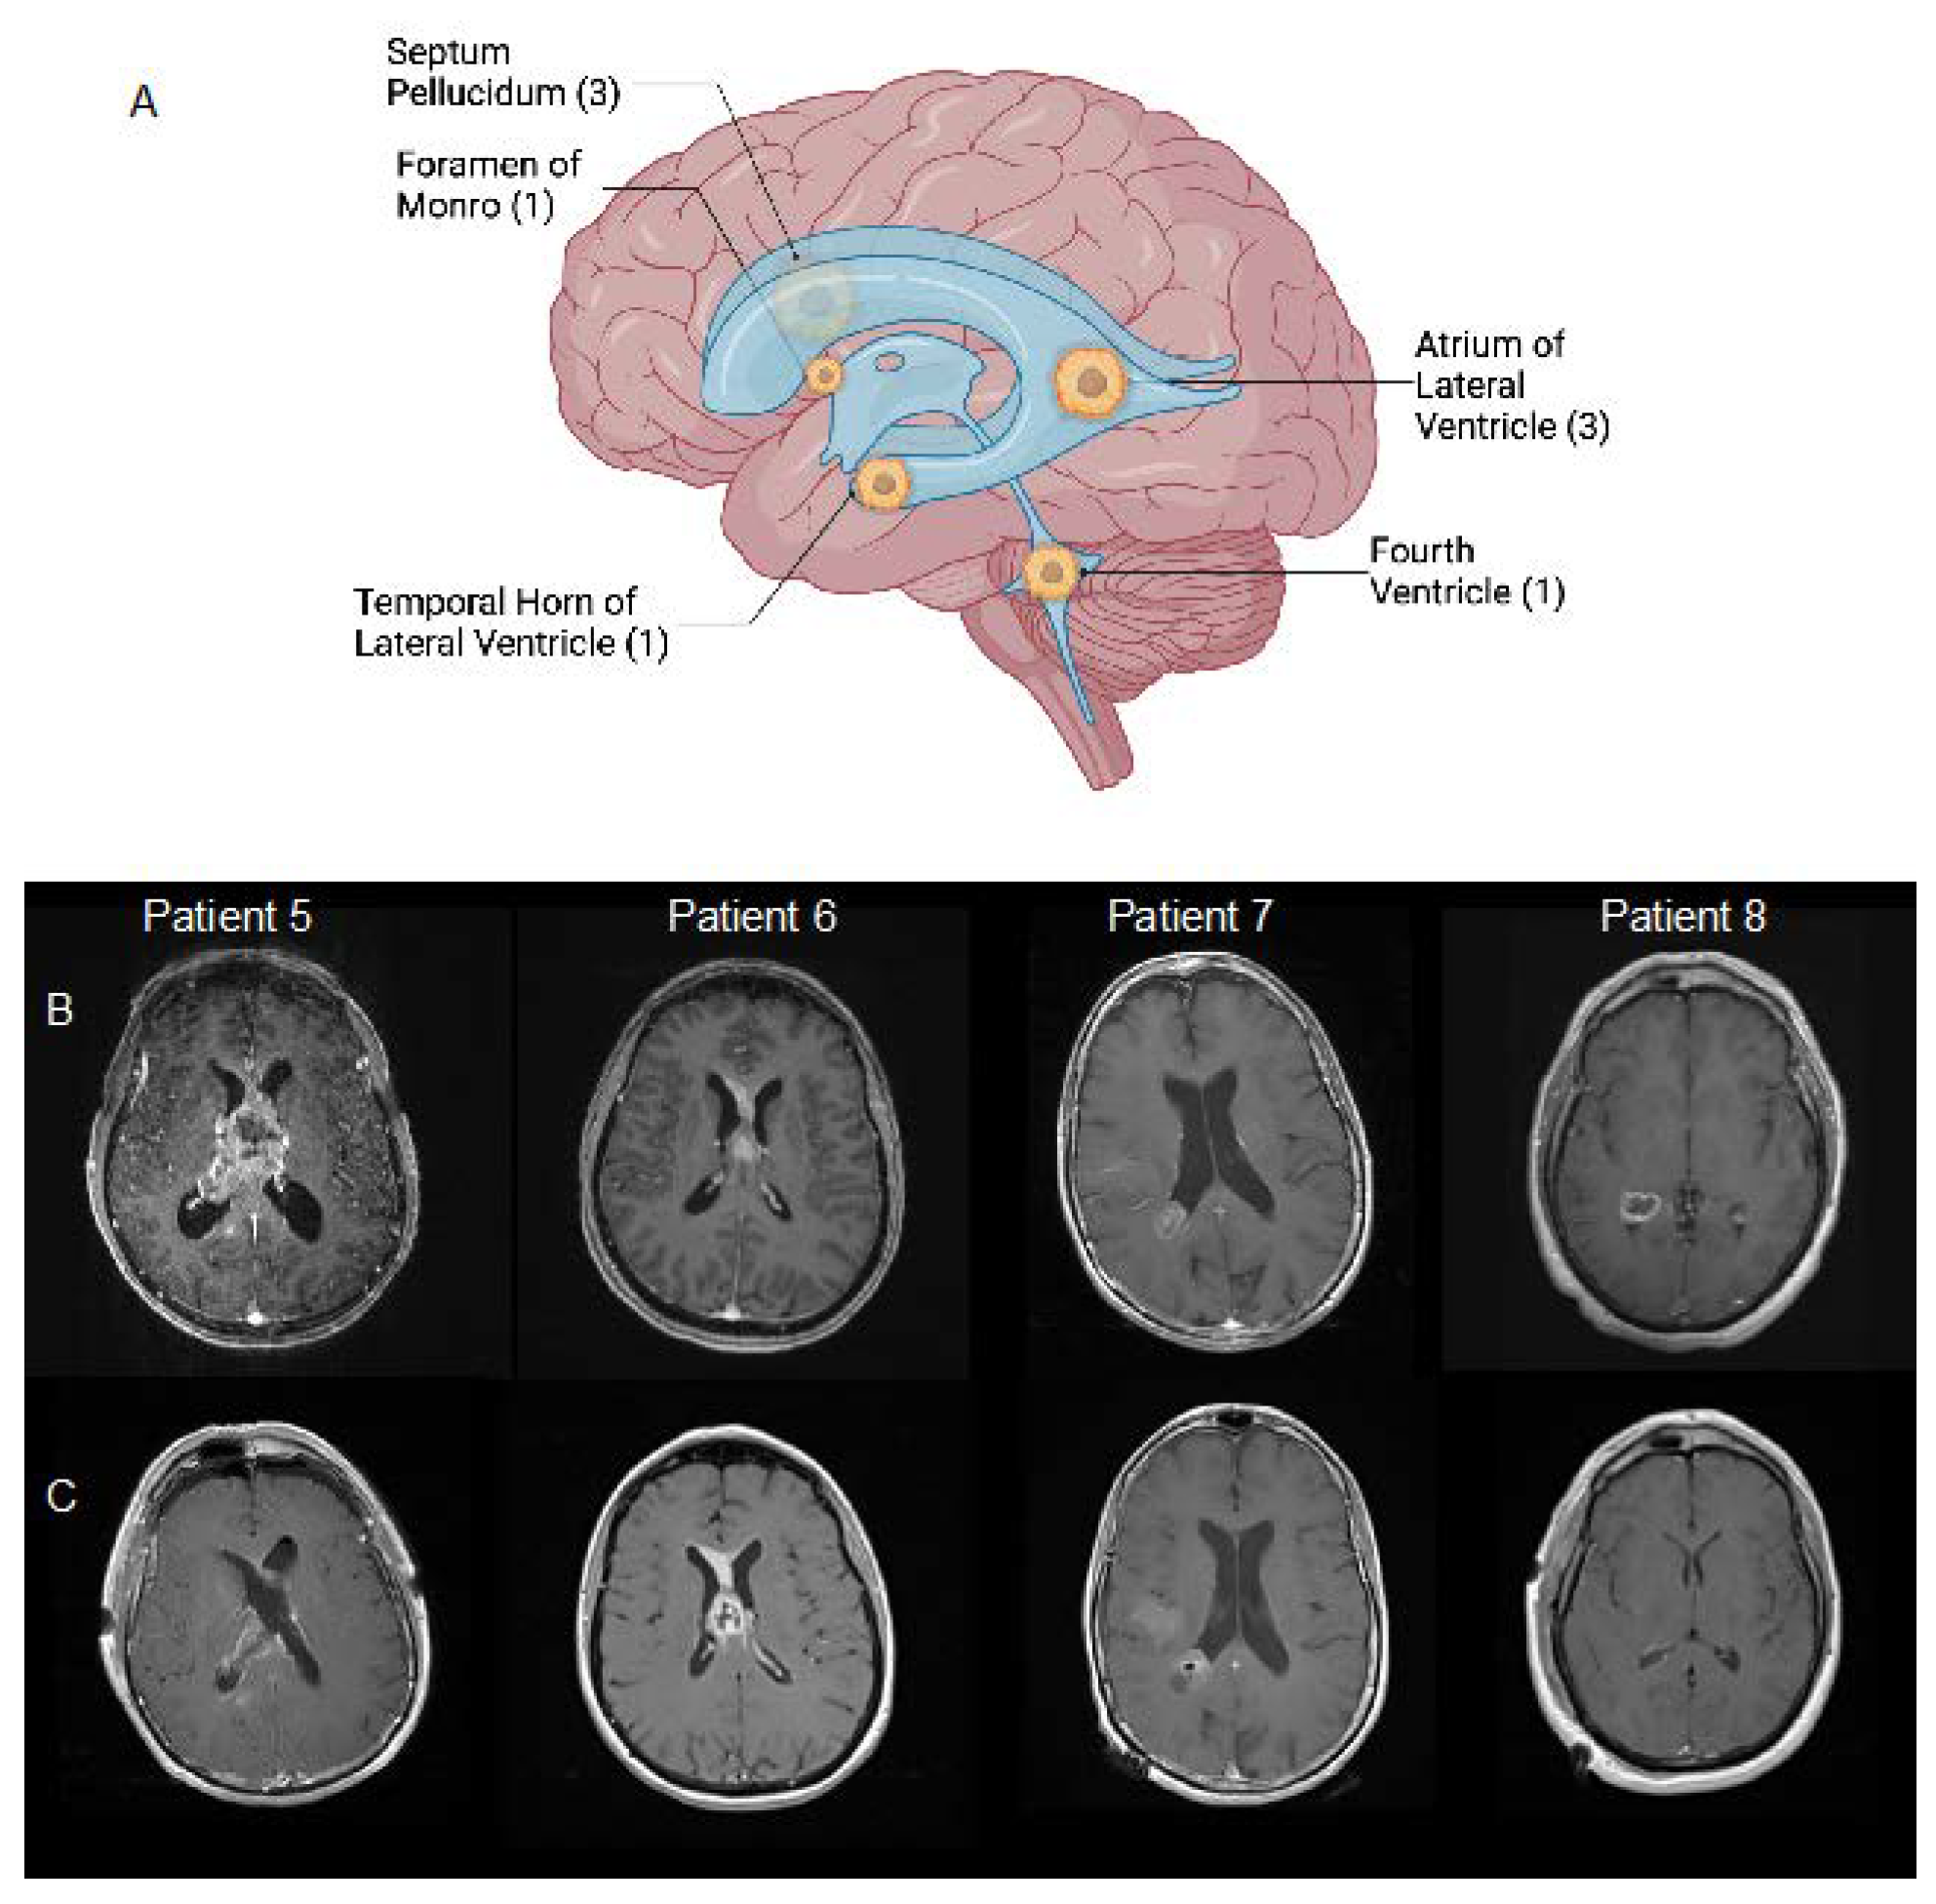

| Patient | Age, y | Sex | Presenting Symptoms | Location | Surgical Approach | Extent of Resection | Shunt/Drain | Postoperative Complications | Postop LOS (Days) | Adjuvant Therapy | Overall Survival [1] |

| 1 | 57 | M | Seizures, headaches | Temporal horn of right lateral ventricle | Right temporal transcortical | STR | None | Unknown | 3 | Unknown | Lost to follow-up |

| 2 | 65 | M | Confusion, memory deficit | Septum pellucidum | Right anterior transcallosal | GTR | EVD | Prolonged intubation, seizure, pulmonary embolism, sepsis, renal insufficiency, atelectasis | 36 | None | 36 days |

| 3 | 37 | M | Headache, ophthalmoplegia, facial droop, ataxia | Fourth ventricle | Suboccipital transvermian | STR | None | Temporary swallowing deficit with PEG, hemiplegia, new cognitive deficit | 18 | RT only (5840 cGy) | Lost to follow-up |

| 4 | 71 | M | Confusion, memory deficit | Septum pellucidum | Right frontal transcortical | STR | EVD | Pulmonary emboli, NSTEMI | 17 | RT (6000 cGy)/TMZ | 5 months |

| 5 | 77 | M | Confusion, memory deficit | Septum pellucidum | Right frontal transcortical | STR | EVD | Prolonged coma | 12 | None | 19 days |

| 6 | 61 | F | Headache, confusion, memory deficit, sleepiness | Foramen of Monro | Stereotactic needle biopsy | Biopsy | VP shunt | Pulmonary embolism; intracranial hemorrhage | 4 | RT (6000 cGy)/TMZ | 4 months |

| 7 | 68 | F | Transient ischemic attack | Atrium of right lateral ventricle | Right parietal transcortical | STR | None | Hearing loss | 2 | RT (6000 cGy)/TMZ + TMZ x2 cycles | 5 months |

| 8 | 56 | M | Confusion | Atrium of right lateral ventricle | Right temporal transcortical | GTR | None | None | 2 | :SVZ RT (6000 cGy)/TMZ [2] | 16 months |

| 9 | 69 | M | Headaches, nausea/vomiting, confusion, memory deficit | Atrium of right lateral ventricle | Right anterior transcallosal | STR | None | New sensory deficit | 15 | None | 18 days |